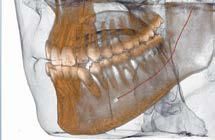

Nell’ambito della radiologia 3D ortopedica, il centro diagnostico utilizza il nuovissimo macchinario NewTom 5G XL, in grado di individuare con la massima precisione la presenza di fratture o lussazioni delle articolazioni, controllare la corretta guarigione di una frattura, valutare una lesione o una ferita causata da infezione, artrite o crescita anormale dell’osso.

Il tutto mediante una semplice e veloce scansione, grazie alla quale si otterranno diverse immagini in 3D ad altissima risoluzione e, per ottenere immagini ancora più nitide mediante un bassissimo dosaggio di radiazioni, gli esperti si avvalgono dell’innovazione racchiusa nella tecnologia Cone Beam.

Se con la radiologia tradizionale era necessario eseguire scansioni multiple, la novità introdotta dal macchinario NewTom 5G XL risiede nella capacità di fornire immagini ad alta risoluzione in un’unica scansione, mostrando nitidamente i dettagli delle articolazioni degli arti superiori e inferiori. Inoltre, a differenza della tecnologia 2D, la radiologia 3D ortopedica permette di individuare immediatamente alcune patologie come quella del metatarso, la quale richiede un allineamento visivo dedicato o una diagnosi delle micro fratture ossee.